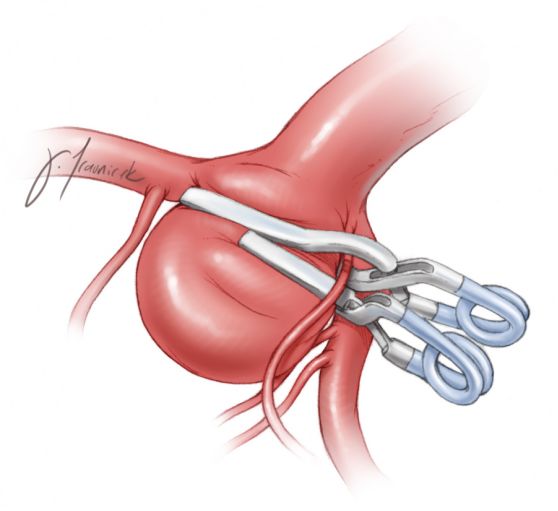

图15: 图示以向上堆的串联方式夹闭基底动脉分叉部动脉瘤。首先放置近端临时开窗夹,夹闭动脉瘤颈的远端部分,改善对动脉瘤解剖关系的观察。第二个直形夹放置在开窗夹远端,夹闭动脉瘤颈的残余部分并重建瘤颈,同时也使笔者更有把握调整小的瘤夹来保护穿支动脉。